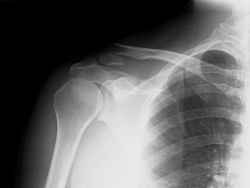

It is easy to feel the collarbone in the body, between the neck and the shoulders. This is because, unlike other bones in the body which are covered with muscles, the collarbone lies very close to the skin. This also makes the collarbone increasingly prone to a number of injuries, fractures, and resultant pain. In fact, clavicle fractures are the most common instances of broken bones, especially in football, and hockey players. Here are some of the common causes, and symptoms of collarbone pain.

Collarbone injuries that lead to a broken collarbone or fractures, are caused by sports injuries, falling on the shoulders, or on the outstretched hand when breaking the fall. Vehicle accidents, or direct blows to the shoulder can lead to injuries to the clavicle.

A collarbone fracture can cause extreme pain to the upper chest and shoulders, especially during movement. The person may be unable to move his or her arms. Sometimes, forced movement can cause a popping, or a clicking sound. Due to the absence of muscular cover, the obvious bone deformity is visible as a lump on the shoulder, or along the bone where there is a fracture. This can be accompanied by swelling, bruising and tenderness in the affected part. The extreme pain can also cause nausea and dizziness.